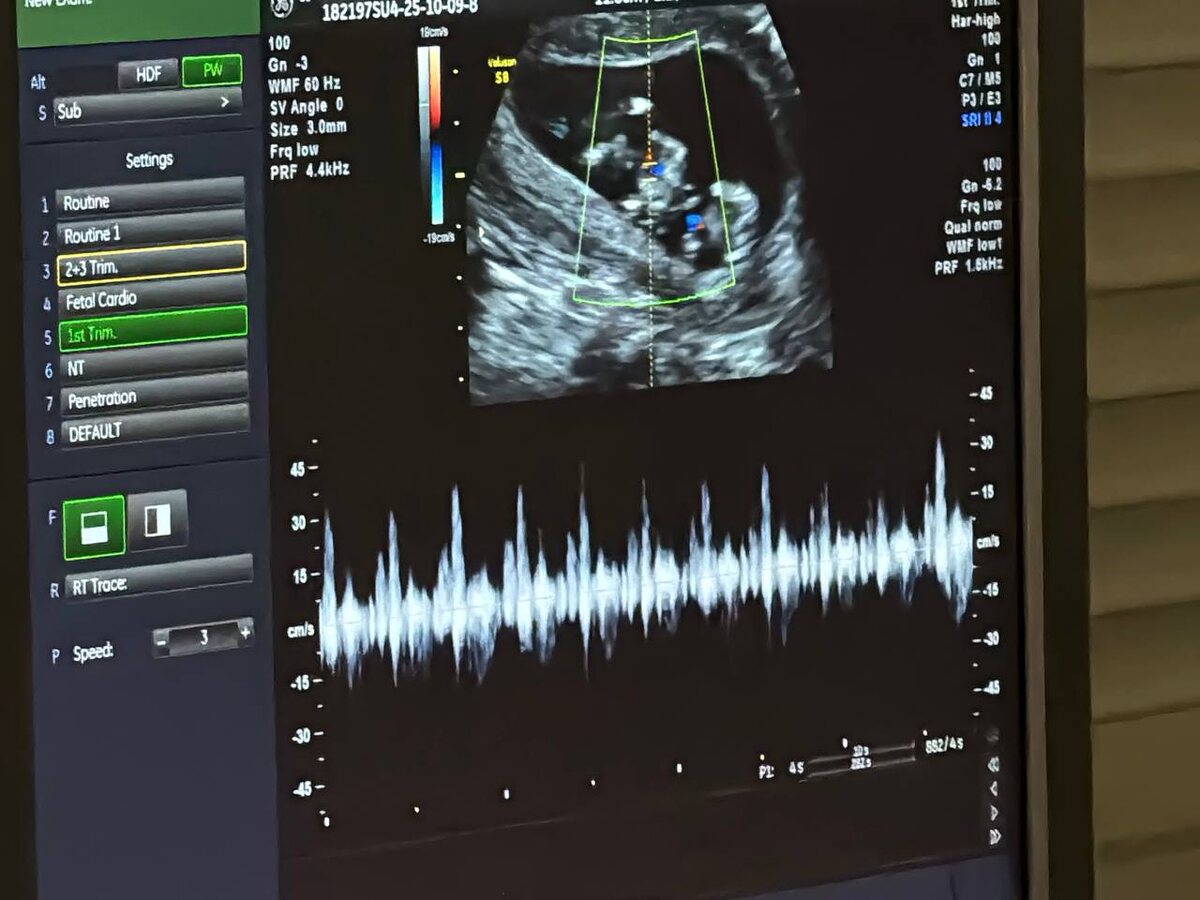

Благодаря внедрению современных методов пренатальной диагностики уровень детской смертности в Костромской области за последние 10 лет сократился почти в два раза. Об этом сообщили в региональном центре охраны здоровья семьи и репродукции, где губернатору Сергею Ситникову представили результаты обновления диагностического оборудования. Система охраны материнства и детства в Костромской области строится на принципе раннего выявления возможных патологий. Уже на этапе беременности будущие мамы проходят бесплатное обследование в центре семьи и репродукции при родильном доме. Здесь проводят комплексную диагностику, включая первый скрининг на сроке 11–13 недель, который выполняют специалисты высшей квалификации. Ежегодно в регионе выполняется более 6 тысяч таких исследований. «Очень радостное и волнительное событие. Все прошло хорошо. Грамотные врачи, хорошее отношение, никаких очередей. Доктор все подробно рассказал, как обстоят дела. И фотографию дал с собой», - поделилась костромичка Анна

Система охраны материнства и детства в Костромской области строится на принципе раннего выявления возможных патологий. Уже на этапе беременности будущие мамы проходят бесплатное обследование в центре семьи и репродукции при родильном доме. Здесь проводят комплексную диагностику, включая первый скрининг на сроке 11–13 недель, который выполняют специалисты высшей квалификации. Ежегодно в регионе выполняется более 6 тысяч таких исследований.

Отдельное внимание уделяется беременным с повышенным риском, включая многоплодные беременности. По словам врача ультразвуковой диагностики Владимира Хохолина, современное оборудование позволяет с высокой точностью определять состояние плодов и вовремя выявлять возможные отклонения.

В частности, жительница Кологрива Екатерина приехала на обследование вместе с супругом. На месте в центре репродукции вместе с будущими родителями губернатор Сергей Ситников послушал, как бьются сердечки малышей.